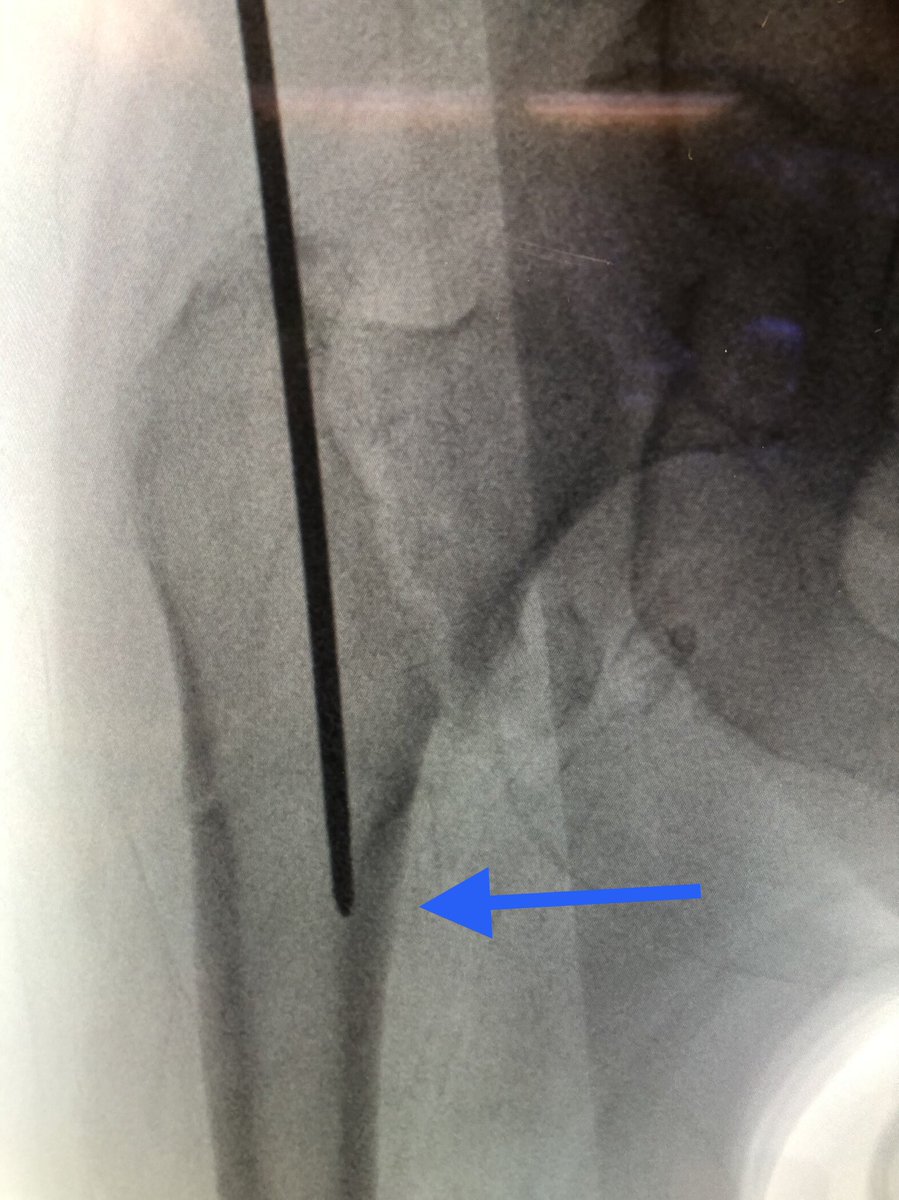

[15/18] I always try to build in some compression. The place to watch is the inferior medial portion of the fracture (arrow). Don’t overdo it or the nail starts to migrate medially.